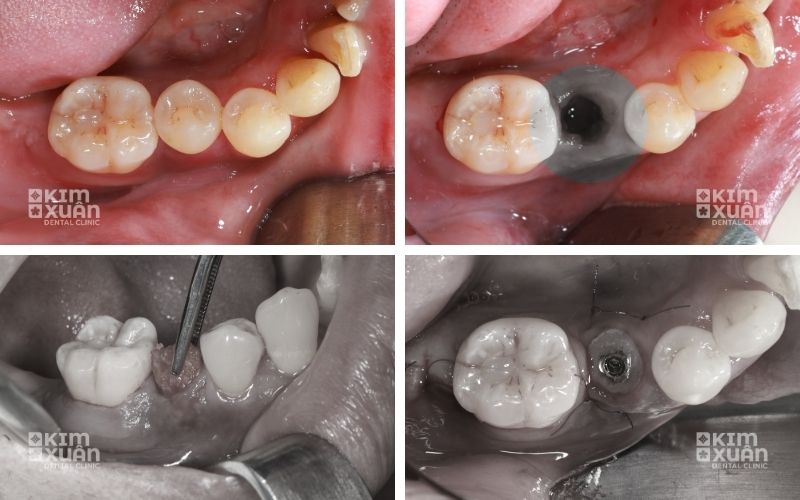

7. Quy Trình Ghép Xương Răng Trong Cấy Implant

Quy trình ghép xương răng implant được thực hiện theo các bước tiêu chuẩn nhằm đảm bảo an toàn, chính xác và hạn chế tối đa cảm giác đau cho bệnh nhân. Toàn bộ quá trình thường diễn ra nhanh chóng và được kiểm soát chặt chẽ bởi bác sĩ chuyên môn.

Bước 3: Tiến hành ghép xương

-

Gây tê tại chỗ (hoặc tiền mê nếu cần)

Mở nướu và đặt vật liệu xương vào vùng thiếu hụt

Khâu đóng và sát trùng cẩn thận

Thời gian thực hiện: khoảng 30 – 60 phút

Trong quá trình này, bệnh nhân hầu như không cảm thấy đau